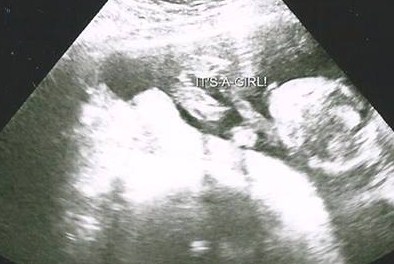

Boy or girl?

Was told by tech it was girl but the three lines are not close together and it was only at 17 weeks. Could this still be possibly a boy since the lines are not close together? Anatomy scan at 22 weeks the baby had its legs crossed, but tech still said girl because she didn't see "anything hanging down." Please let me know ur thoughts on this.Attachment 19839

I've been told that by a lot of people that they think it looks girly, but the angle that the tech looked is very odd and they only looked at it for like two minutes. We've already painted the room pink and made out baby shower invites for a girl. My husband wanted a boy, but is now excited about having a girl. Just hope to get some more insight on if this could still turn to be a boy since the three lines are not close together.

this is the only one i have the tech only looked for gender for like 2 minutes and said girl. I've seen where a boy can show 3 lines, so not for sure if this can still possibly be a boy or not? I mean it looks like three lines but the third line is way on the other side.

Anything is possible...and I have seen girls turn into boys...but never the other way around LoL Can you do another elective ultrasound to confirm? I can imagine the feeling of not thinking the tech took enough time with you. I'd consider another US for more confirmation